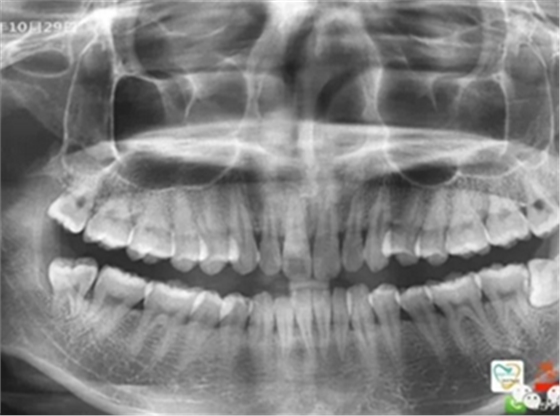

由于智齒的生長(zhǎng)位置特殊,導(dǎo)致了拔除難易不同,如智齒出現(xiàn)橫著長(zhǎng)或者靠近牙神經(jīng)的話,則難度會(huì)較高,一般人只需拍個(gè)口腔全景片,但相對(duì)于智齒靠近神經(jīng)管的情況,還可能需要拍CT,這都很考驗(yàn)牙醫(yī)的技術(shù)。

下面這兩張圖,據(jù)說拔牙費(fèi)時(shí)1.5小時(shí),收費(fèi)14000元。